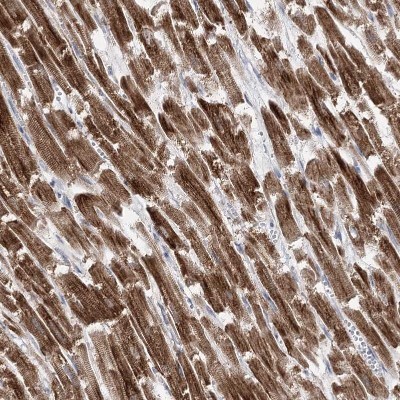

- Immunohistochemistry-Paraffin: Pyruvate Dehydrogenase E1 beta subunit Antibody [NBP1-87421] - Staining in human heart muscle and pancreas tissues using anti-PDHB antibody. Corresponding PDHB RNA-seq data are presented for the same tissues.